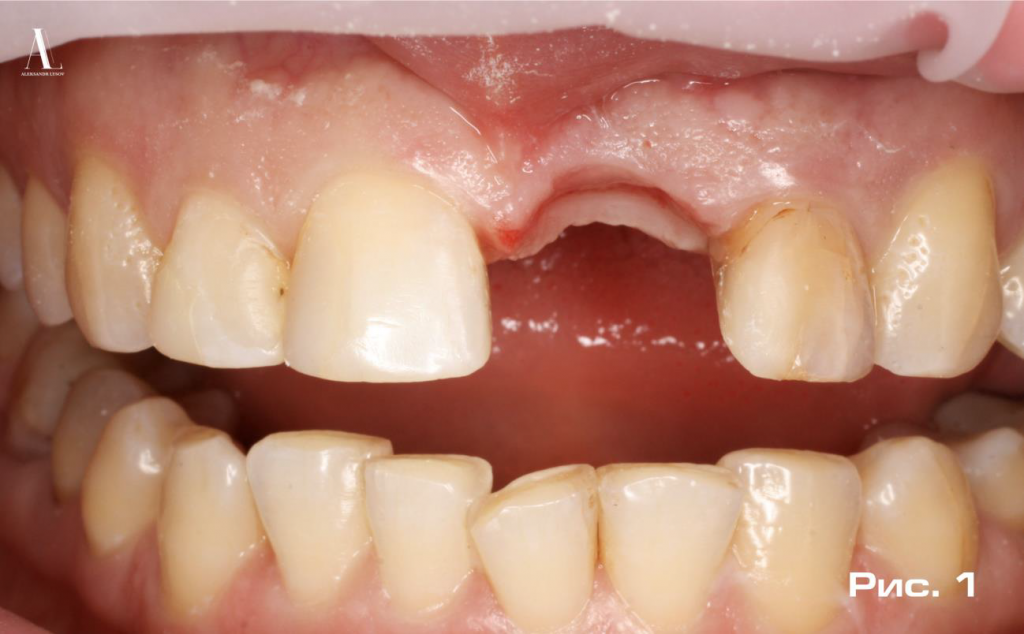

Пациентка М. (48 лет) в Октябре 2017 года обратилась в Самарский стоматологический центр «DAS-clinic» с жалобами на эстетический и функциональный дискомфорт, вызванный отсутствием зуба 2.1 (Рис.1).

При сборе анамнеза выяснилось, что зуб был удален за два месяца до обращения в клинику по причине осложнений, возникших в процессе эндодонтического лечения. Сопутствующие заболевания отсутствовали, противопоказаний к имплантологическому лечению не выявлено.